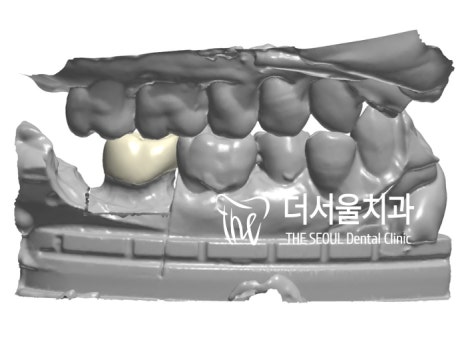

구강 스캐너로 환자의 구내를 본뜬 다음

컴퓨터 분석을 사용하여

보철을 제작하는 방식이라 할 수 있습니다.

아날로그 방식에 비해 훨씬 정확한 것은 물론이며

완성도 높은 보철을 만들 수 있다는 점!

지대치의 형태가 나오게 되면은,

인상채득(Impression)을 하고 CAD/CAM을

사용하여 보철 디자인을 진행합니다.